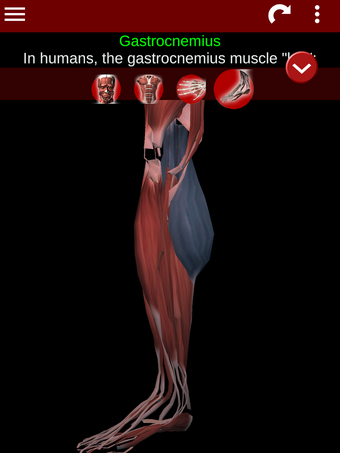

Esta herramienta educativa proporciona una descripción de cada músculo del cuerpo humano, así como un modelo tridimensional del sistema muscular. Con sólo tocar con el dedo, la aplicación revelará la información pertinente.

Los usuarios pueden hacer zoom sobre el músculo, así como elegir si ocultar o mostrar los datos. La orientación puede ser horizontal o vertical, según convenga más.